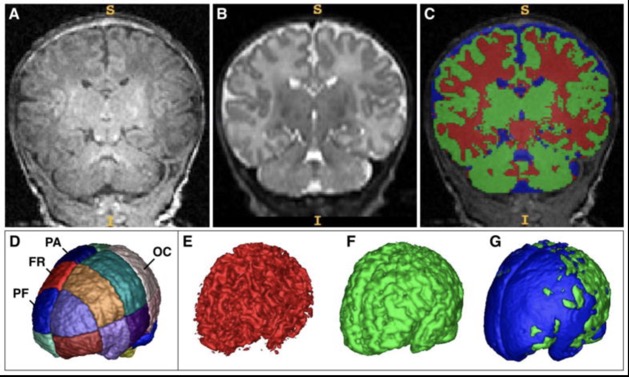

1. volume total de matière grise (GM) plus faible en particulier dans les régions cérébrales préfrontales et frontales.

2. volume total de liquide céphalo-rachidien (LCR) plus élevé en particulier dans les régions préfrontales, frontales et pariétales, mais pas occipitales